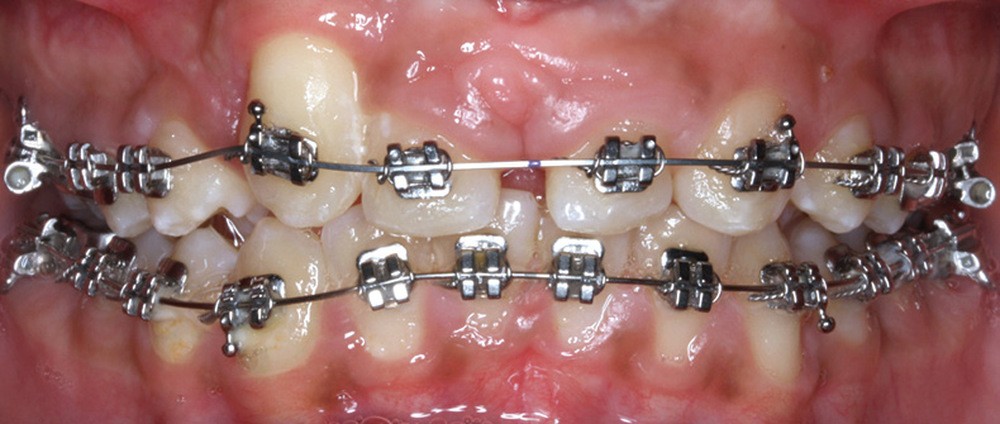

Dans un premier temps, l’extraction des 11 et 21 est réalisée. Un bouton est collé sur la 13, visible dans l’alvéole de la 11 afin de permettre sa désinclusion (fig. 2). La traction se fait à l’aide d’un arc TMA .016 x .022 en overlay afin d’avoir un axe de traction horizontal et vestibulaire évitant une résorption de la 12 à cette étape (fig. 3a,b) [3]. Ne pouvant pas mettre d’arc de Nance du fait de la position palatine des incisives latérales, il est convenu que des minivis d’ancrage peuvent être nécessaires si une perte d’ancrage postérieure est constatée (ce qui n’est pas le cas).